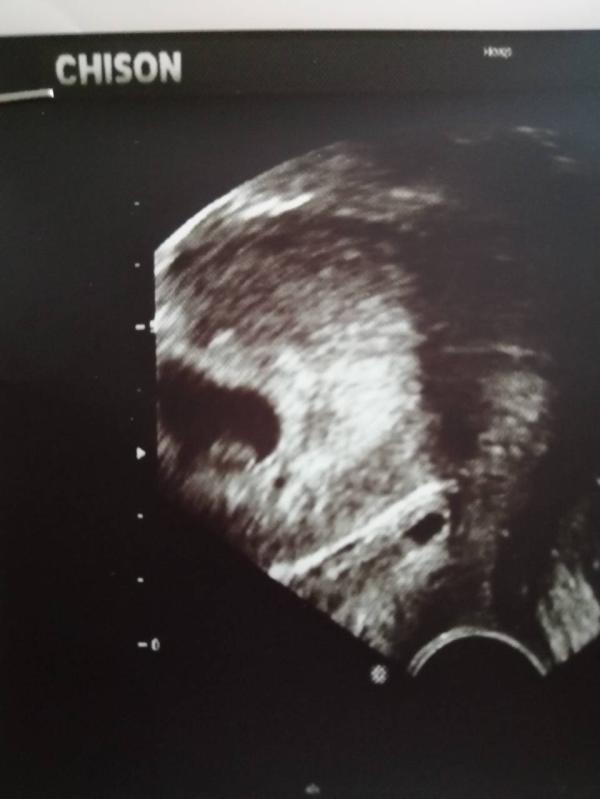

УЗИ сердечка: все хорошо! Растем и развиваемся, заключение без цифр, но главное — здорово

Сходила на узи, послушала сердечко, все у нас замечательно. Растем. В заключении правда не написали сколько ударов, ну не суть, главное все ок.